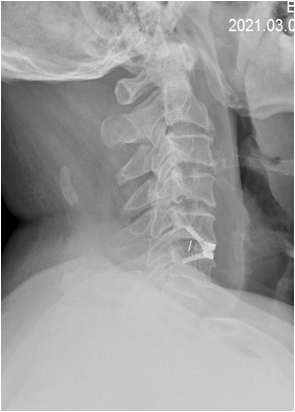

术后 图片2